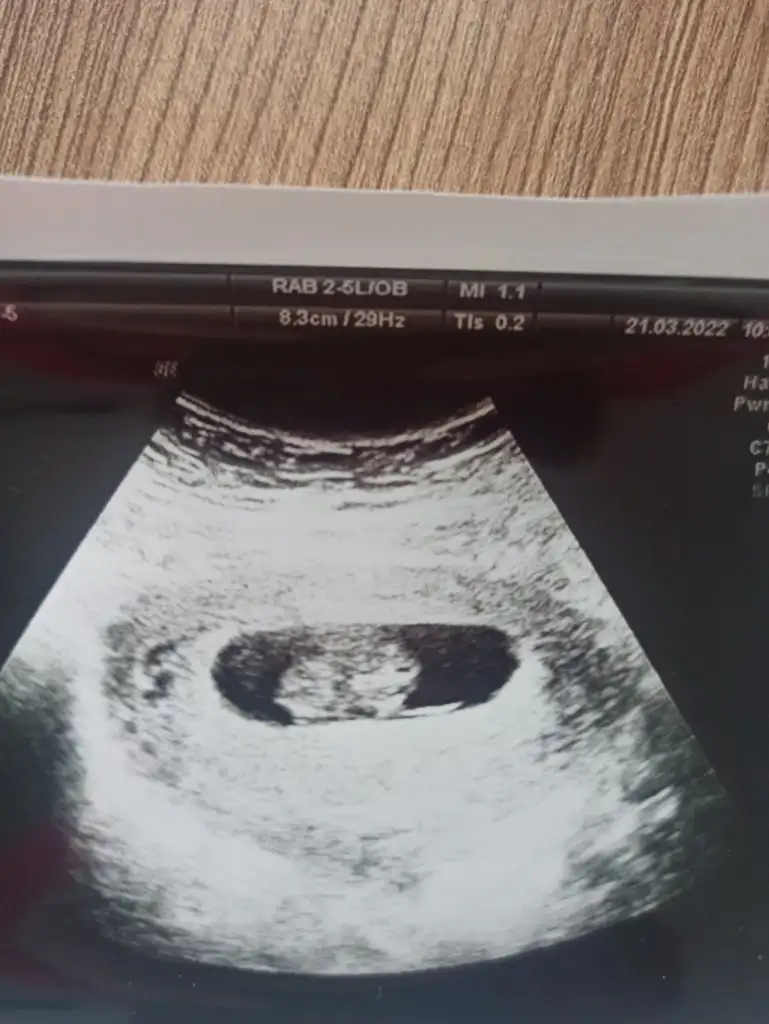

tahmın alabilir miyim karından ultrason 10+2🌸❤️